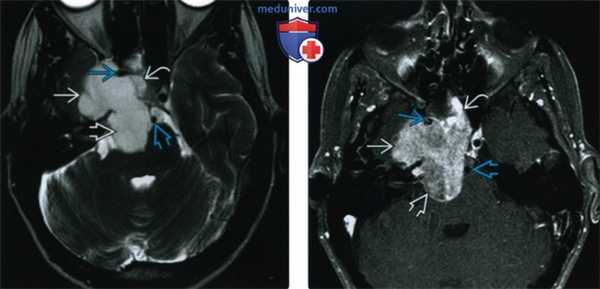

(Слева) При МРТ Т2ВИ в аксиальной проекции у этого же пациента регистрируется неоднородный средней интенсивности сигнал (опухоли) с участками более интенсивного сигнала, которые могут являться очагами некроза. Криволинейная низкоинтенсивная зона, вероятно, представляет собой участок кальциноза опухолевой ткани.

(Справа) При аксиальной КТ в костном окне у этого же пациента видно, что перед нами преимущественно литическая остеосаркома. Отмечается некоторое расширение ската затылочной кости, позади него определяется обширная зона деструкции кости. Остеоидного матрикса в ткани опухоли не наблюдается.